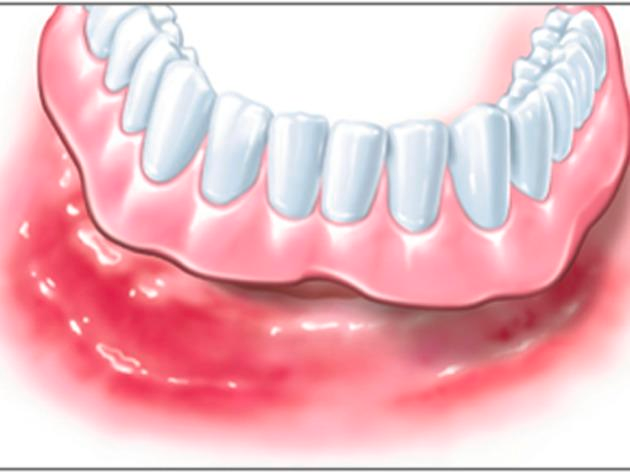

Zahnloser Kiefer

Wenn Ihnen im Unterkiefer fast alle oder sogar alle Zähne fehlen, haben Sie mit Implantaten trotzdem gut lachen. Denn schon zwei bis vier Implantate reichen aus, um einer Vollprothese festen Halt zu geben. Die Befestigung erfolgt mit speziellen Haltesystemen, die aus zwei Elementen bestehen. Eines wird dauerhaft auf die Implantate gesetzt, das Gegenstück in die Prothese eingearbeitet.

Beim Einsetzen verbinden sich die beiden Elemente, ähnlich wie bei einem Druckknopf: Ihre Prothese sitzt fest. Zum Reinigen können Sie sie jederzeit leicht wieder abnehmen.

Auf mindestens sechs Implantaten kann auch eine Brücke dauerhaft an Ihrem Kiefer verankert werden. Der Zahnersatz sitzt dann so fest, dass auf den stützenden rosa Prothesenkunststoff verzichtet werden kann. Im Oberkiefer bleibt in jedem Falle der Gaumen frei von Prothesenmaterial.

So genießen Sie in jeder Situation völlige Sicherheit, denn nichts kann sich unverhofft lösen. Mit Ihren implantatgetragenen Dritten können Sie essen, reden und lachen, als ob es Ihre Zweiten wären.